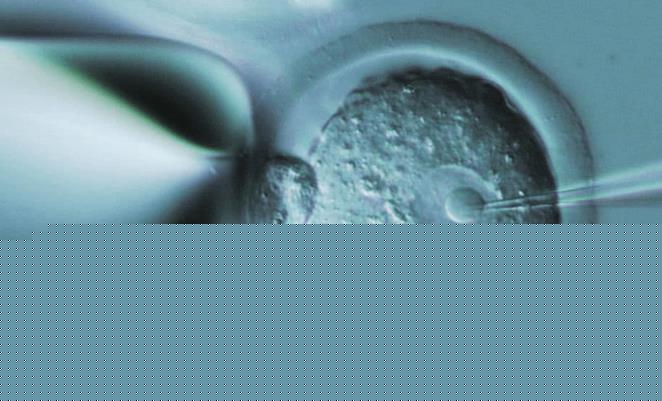

台湾试管成功率

台湾送子鸟供卵试管费用

台湾试管婴儿的费用是多少